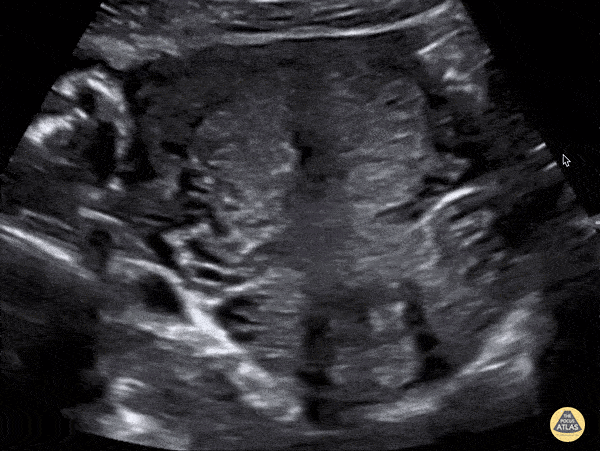

OB/Gyn - IUD in Transverse Plane

Patient came to the ED due to flank pain. Renal ultrasound was performed by me with the US team. Upon looking for the bladder, I saw my first IUD via US which appeared hyperechoic. ParaGard has been shown to be more than 99% effective. Mehtab Galeh, MD, @GalehMehtab